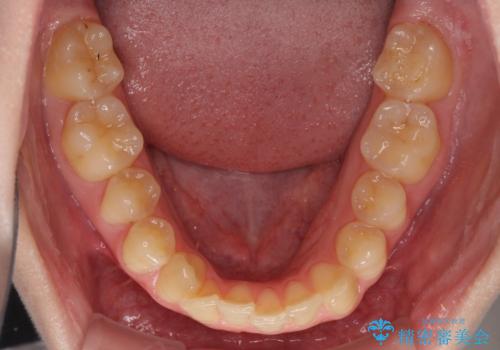

- 著しい八重歯を気にして来院された患者様です。

片側の八重歯であり上顎の正中がずれていたため、上顎左右第一小臼歯2本を抜歯して排列することとしました。

下顎の骨格的なズレが大きかったため、上下歯列のバランスが取れるか心配でしたが、上下ともに左右対称に近い歯列で治療を終えることができました。